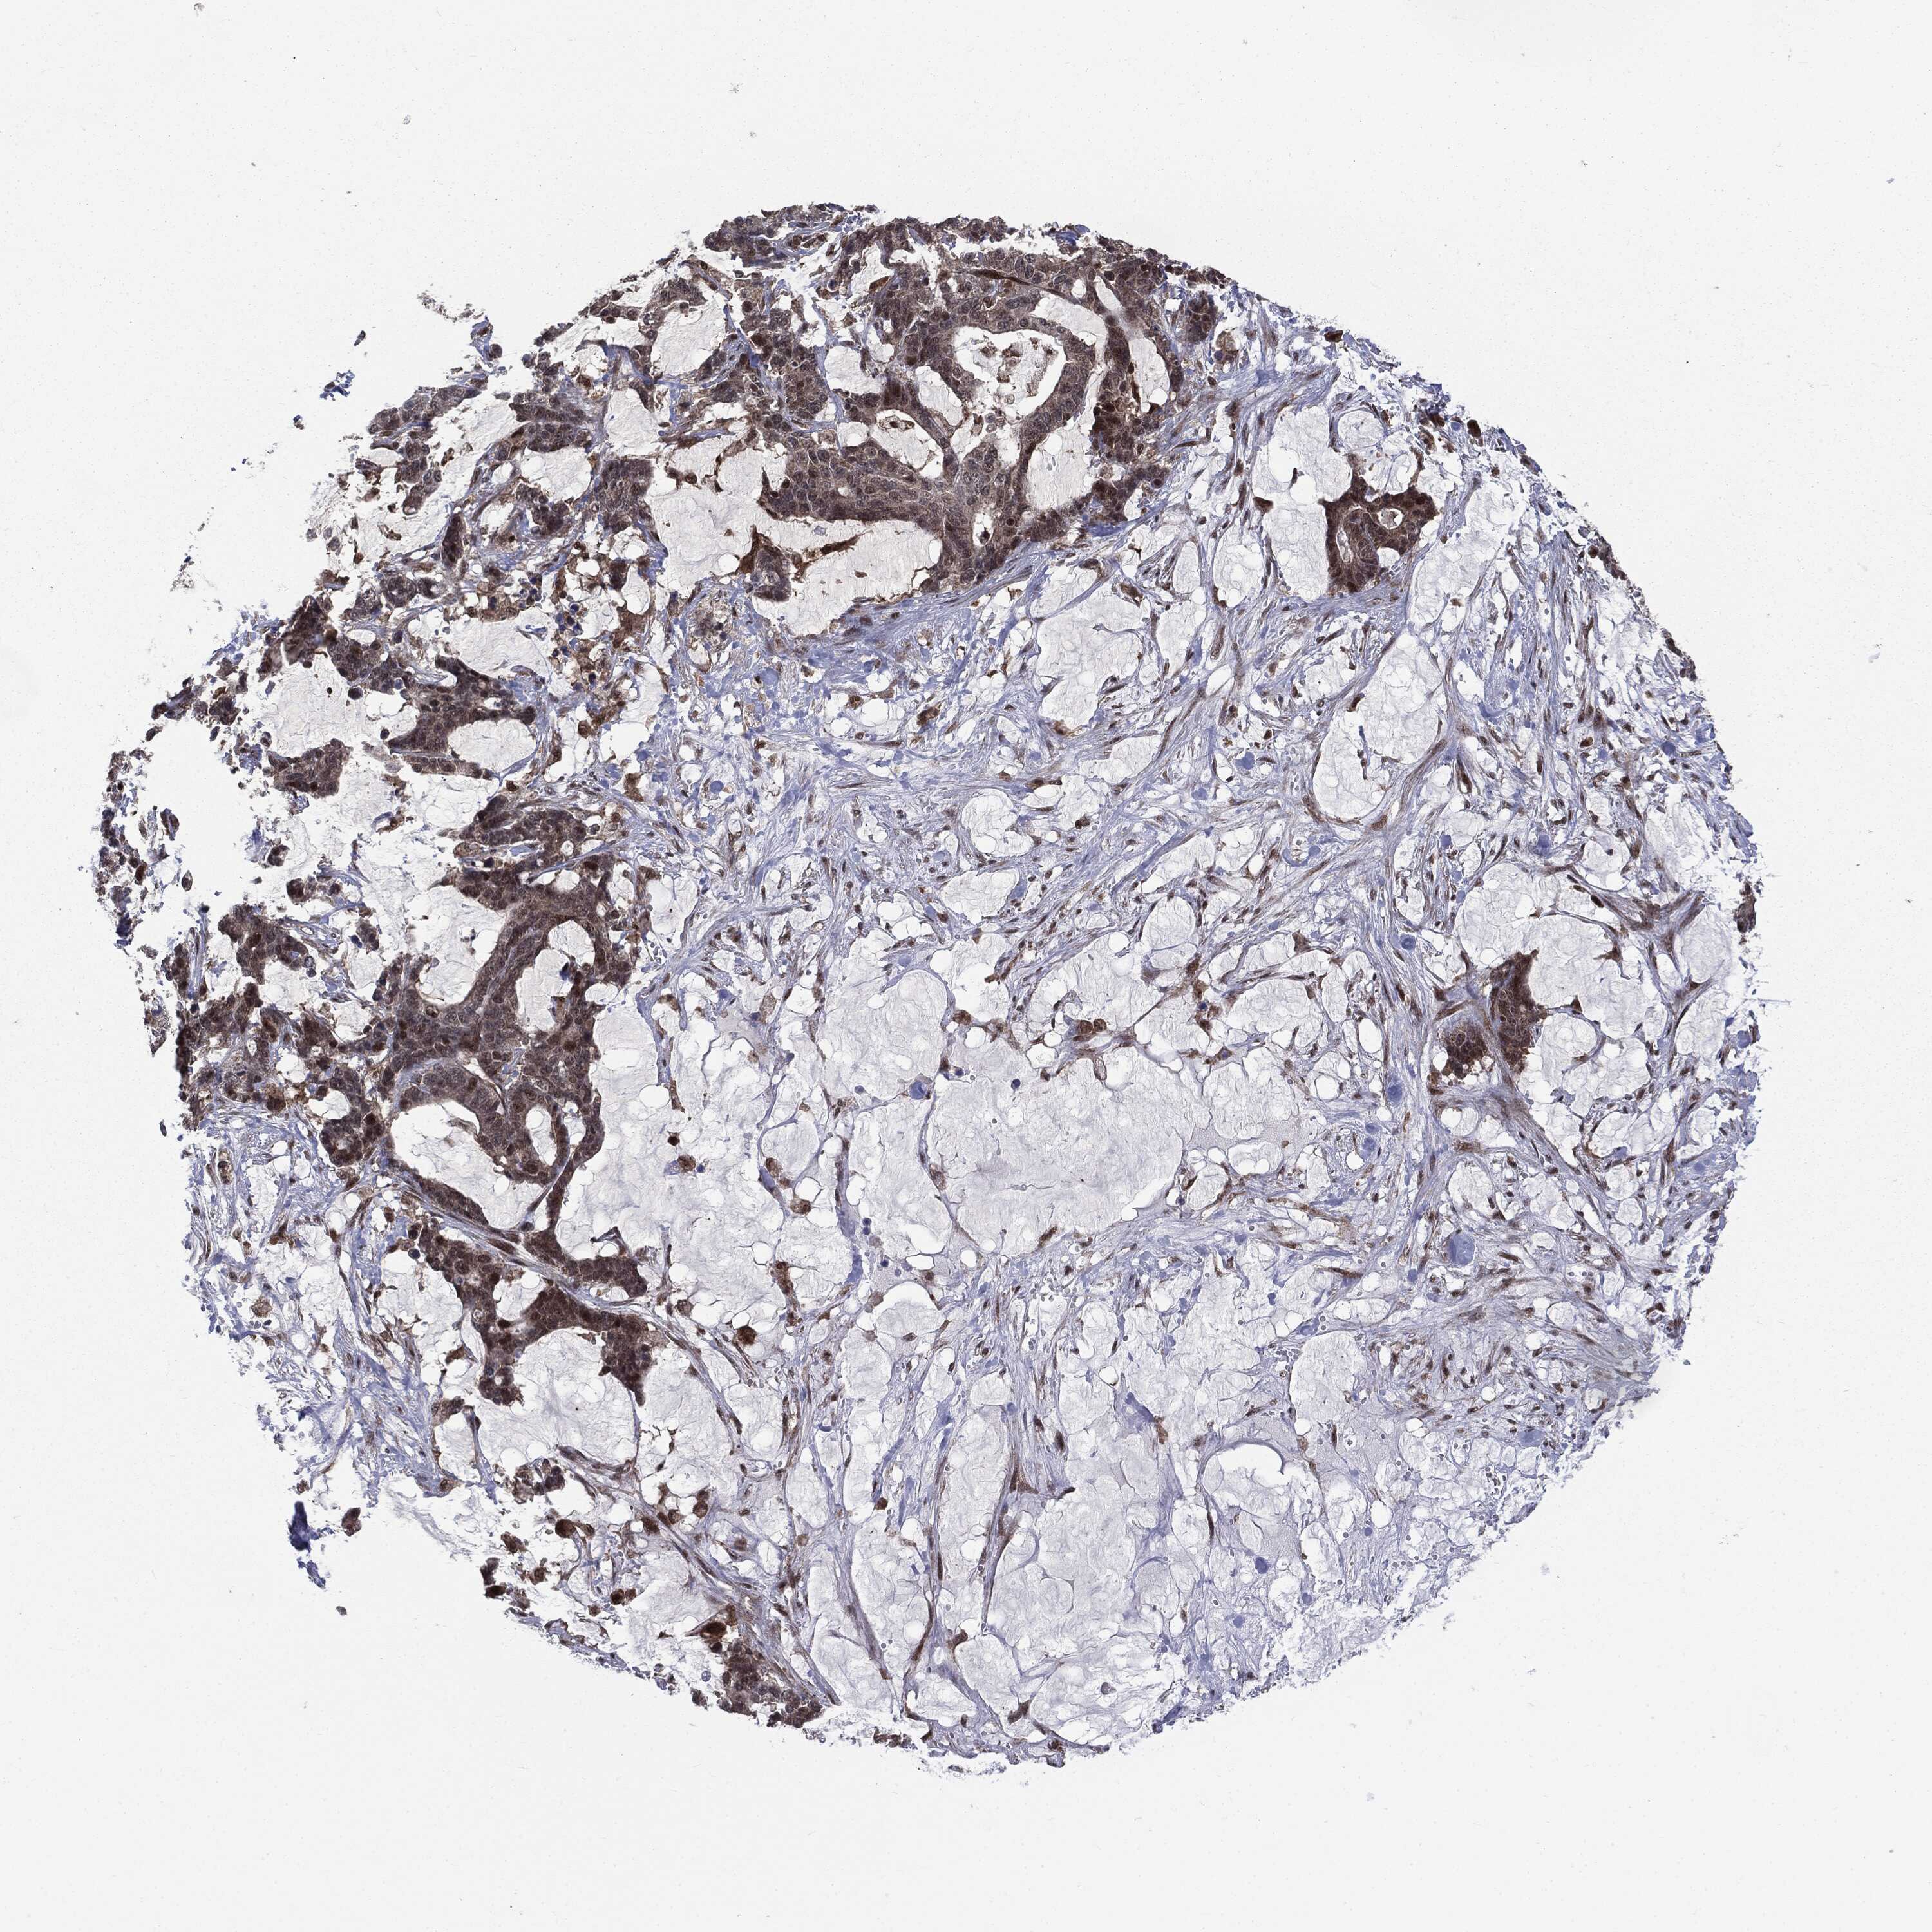

STOMACH CANCER - Protein expressioni

A mouse-over function shows sample information and annotation data. Click on an image to view it in a full screen mode. Samples can be filtered based on level of antibody staining by selecting one or several of the following categories: high, medium, low and not detected. The assay and annotation is described here.

Note that samples used for immunohistochemistry by the Human Protein Atlas do not correspond to samples in the TCGA dataset.

Antibody stainingi

Antibody staining in the annotated cell types in the current human tissue is reported as not detected, low, medium, or high, based on conventional immunohistochemistry profiling in selected tissues. This score is based on the combination of the staining intensity and fraction of stained cells.

Each image is clickable and will lead to virtual microscopy that enables deeper exploration of all samples and also displays staining intensity scores, fraction scores and subcellular localization as well as patient and tissue information for each sample.

HPA005695

CAB022068

CAB035999

CAB080052

CAB080054

CAB080098

Staining

High

Medium

Low

Not detected

Intensity

Strong

Moderate

Weak

Negative

Quantity

>75%

75%-25%

<25%

None

Location

Nuclear

Cytoplasmic/membranous

Cytoplasmic/membranous,nuclear

Adenocarcinoma, NOS

Adenocarcinoma, High grade